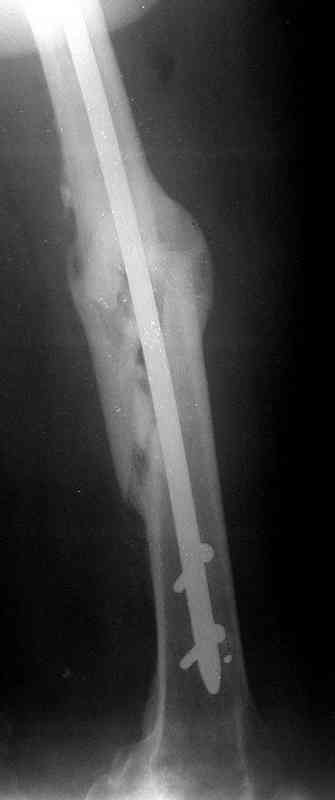

Больной А., 28 лет, поступил в НИИ им. Н.В. Склифосовского 22.12.99 после падения на улице. Жалобы на боли в области левого тазобедренного сустава и левом бедре. Из анамнеза следовало, что 20.06 во время прыжка с парашютом у него возник закрытый оскольчатый перелом средней трети левой бедренной кости со смещением отломков, по поводу чего в одной из ЦРБ Московской области через 3 дня после травмы был произведен открытый интрамедуллярный остеосинтез штифтом типа Кюнчера.

Послеоперационное течение было гладким. Больной ходил при помощи костылей с дозированной нагрузкой на оперированную конечность.При осмотре в НИИ им. Н.В. Склифосовского через 6 месяцев после травмы:

левое бедро и левый коленный сустав несколько увеличены в объеме, отечны, пальпаторно определяется болезненность в средней трети бедра;

по его наружной поверхности послеоперационный рубец - рана зажила первичным натяжением. При измерении длины бедер обнаружено укорочение левого бедра на 4,5 см. На рентгенограммах этого бедра: ось конечности правильная, отмечается захождение основных костных фрагментов по длине, проксимальный конец штифта выступает слишком медиально и высоко относительно большого вертела, периостальная мозоль незначительна.22.12 - через 6 месяцев после операции, произведенной в ЦРБ, нами по поводу замедленно консолидирующего перелома левой бедренной кости с ее абсолютным укорочением под наркозом произведена операция: удаление штифта, закрытый блокирующий интрамедуллярный остеосинтез перелома левого бедра штифтом без рассверливания (UFN) длиной 40 см, диаметром 10 мм с блокированием только проксимальных отверстий (динамический остеосинтез). Наложен аппарат Илизарова на 4 полукольцах с целью удлинения укороченного бедра. Послеоперационное течение без особенностей. Ежедневно осуществляли дистракцию отломков на 1 мм. Через 3 недели после операции больной выпи-сан на амбулаторное лечение с продолжением дистракции отломков. В течение 1,5

месяцев дистракции укорочение левого бедра удалось полностью устранить. 22.02.00, т.е. через 2 месяца после повторного остеосинтеза, больному произведено дистальное блокирование штифта двумя винтами и демонтирован аппарат Илизарова. В течение 2 недель после операции больной ходил с помощью костылей, потом 2 недели с тростью. Опороспособность и функция оперированной конечности полностью восстановились через 4 недели после операции.

Фиксаторы удалены через 12 месяцев после операции, выполненной по поводу замедленной консолидации перелома бедра с его укорочением.